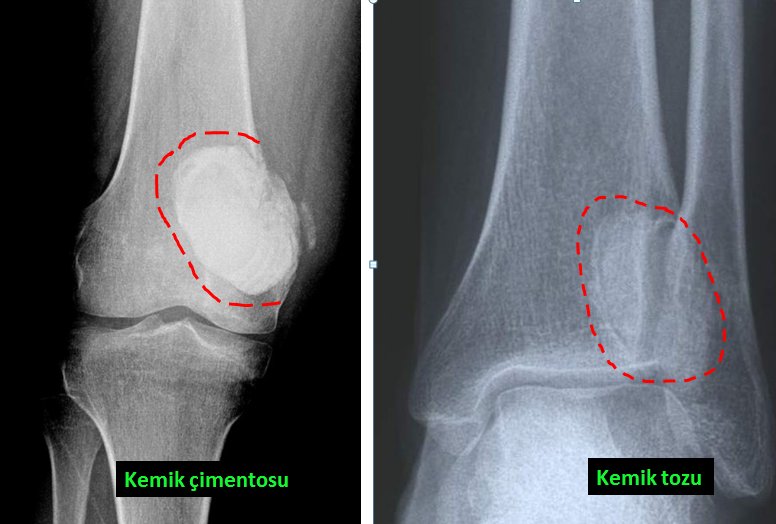

İyi huylu kemik tümörleri ise daha çok kemik kistleri, kıkırdak kökenli bazı tümörler yada dev hücreli kemik tümörü gibi bir takım lezyonlardır. Kistler basit olabileceği gibi kompleks de olabilir. Basit kemik kistleri daha çok çocuklarda görülür. En sık bölge omuz çevresi olmakla beraber her kemikte ortaya çıkabilir (resim-5). Basit kemik kistinin tedavisinde bazı durumlarda ameliyat gerekirken bazen de ameliyatsız tedavi uygulanabilir. Bunun için hastaya ameliyathane şartlarında kist içine enjeksiyon uygulanır ve bunu birkaç kez tekrarlamak gerekebilir (resim-6). Kompleks kist ile anlatılmak istenen ise “anevrizmal” kemik kistidir. Bunun tedavisi sadece cerrahi olup kist temizlendikten sonra içi bir takım özel maddelerle muamele edilmelidir. Oluşan boşluk kemik çimentosu yada kemik tozlarıyla doldurulur (resim-7). Anevrizmal kemik kisti basit kemik kistine göre daha saldırgan bir lezyon olup bazen kemiği tamamen ortadan kaldırabilir. Bunda nüks olasılığı da daha fazladır.

Dev hücreli kemik tümörü de gençlerde daha sıktır. Bu tarz bir tümör en fazla dizde görülmekle beraber vücudun her yerinde ve özellikle eklem bölgelerinde kemiğin içinde oluşur (resim-10). Genellikle son birkaç aydır hissedilen künt ağrı şeklindedir. Tedavisi sadece ameliyat ile yapılabilir. Tümör tamamen kemikten uzaklaştırılır ve boşluk ise kemik çimentosuyla yada kemik tozlarıyla doldurulur (resim-11). Tümörün temizlenmesi işlemi tam olarak yapılmazsa nüks kaçınılmazdır.